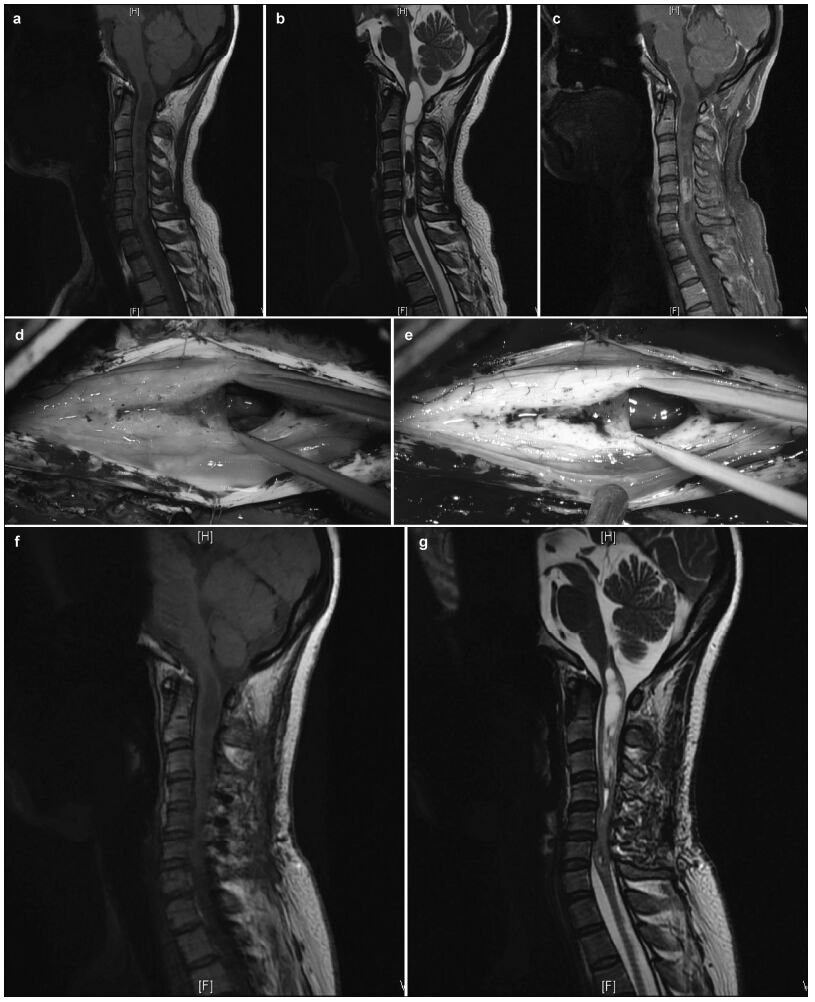

| Figure 2 Pre-and postoperative magnetic resonance imaging of intramedullary ependymomas at C2-T2, and intraoperative observations. (a) Preoperative sagittal T1 image reveals spinal cord thickening. (b) T2 image shows high intramedullary signal intensity at C2-T2, but no signal at either end. (c) Enhanced scanning reveals distinctive enhancement of the tumor mass and cyst wall. Tumor ends, as micrographed using white light (d) and fluorescence (e). (f) Cysts at the tumor ends, microscopically probed with white light, do not show the tumor. (g) Distinct cyst walls are evident under fluorescent illumination, revealing a suspicious tumor that was removed. At 3 months, the sagittal T1 (h) and T2 (i) images and the enhanced scan (j) reveal no evidence of tumor residuals or relapses. |

3 Results 3.1 Intraoperative tumor statusIn the absence of FS, 80 patients demonstrated clear tumor boundaries and 32 had blurry tumor boundaries resulting from tumor adhesion to the spinal cord, including 14 with severe adhesions and intramedullary tumor-associated strokes (Figures 1-3). Under fluorescence, tumors were visible in 94 patients and invisible or indistinct in 18, including 14 with intramedullary tumor-associated strokes and indistinct MRI enhancement and four without MRI enhancement. Under fluorescence, complete tumor removal was accomplished in 92% (103/112) of the patients. Of the nine patients with tumors that could not be completely removed, five had myxopapillary ependymomas at the conus medullaris and four also had strokes and severe adhesions.

3.3 Comparison of imaging and intraoperative fluorescence findingsOf the 112 cases, 94 (83.9%) had enhanced preoperative MRIs and distinct intraoperative fluorescent images, four had indistinct MRI enhancements and fluorescent images during surgery, and 14 had tumor-associated strokes associated with non-uniform MRI enhancement and indistinct fluorescent imaging, intraoperatively (Figure 3). The present study included 90 patients with combined syringomyelia, 88 of whom did not present with cyst wall enhancement during either their preoperative MRI examinations or with intraoperative fluorescent cyst walls, and one who presented with preoperative cyst wall MRI enhancement and intraoperative fluorescent cyst wall images.